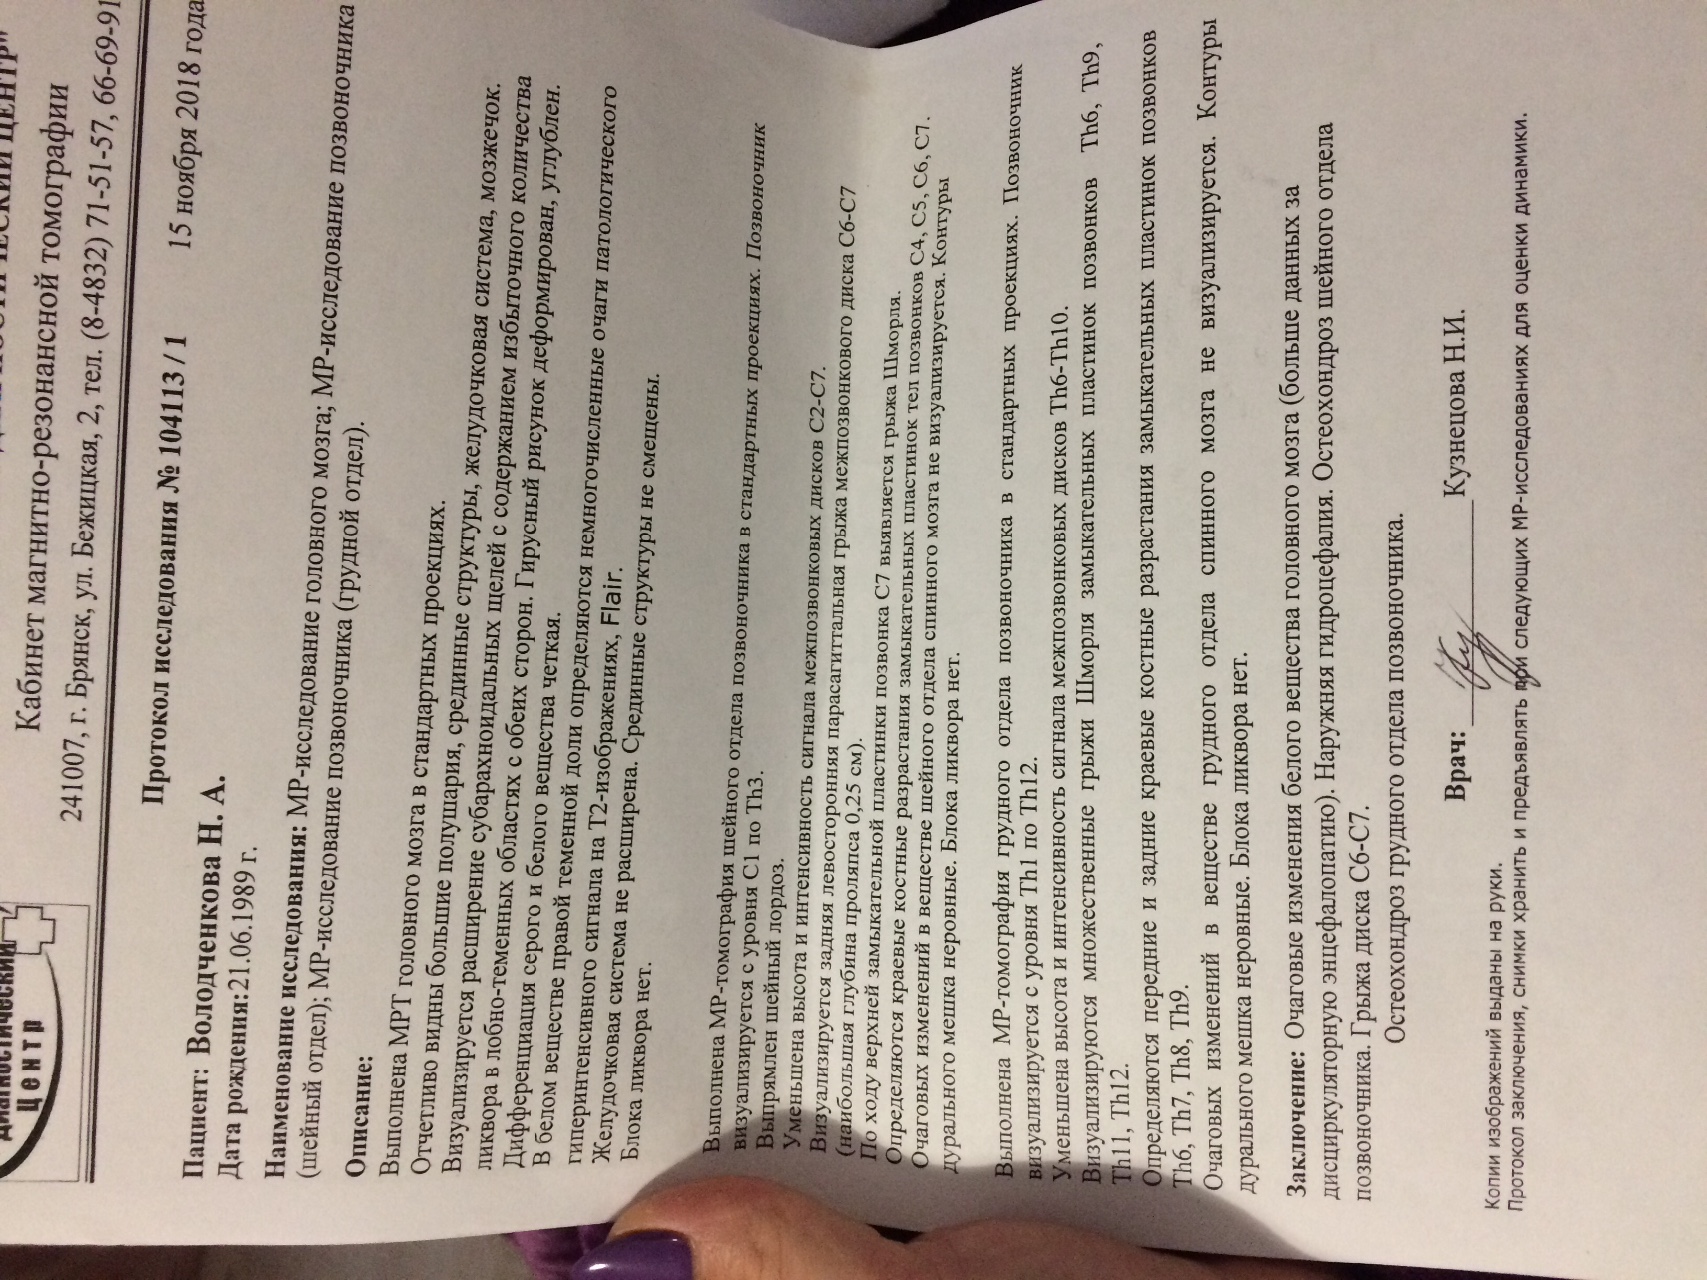

Медицинская диагностика: КТ и МРТ головного мозга

Раздел: Пульс времени